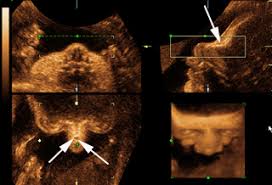

If the 2D ultrasound does not demonstrate two nasal bones then 3D ultasound may be useful. An ultrasound scan There is no risk to the baby from either of these procedures. October 15 2018 Shane Dale According to the National Down Syndrome Society NDSS during the normal fertilization of a womans egg by a mans sperm the resulting nucleus of each cell in a fetus contains 23 pairs of chromosomes half of which are inherited from each parent.

For this reason 3D ultrasound reconstruction of the nasal bone and other facial bones is useful. At this stage the babys legs arms fingers and toes should be fully formed. Mothers should not be encouraged to have an ultrasound called a.

Of the many defects 3D 4D ultrasound has been useful in evaluating the skeletal and cardiovascular systems in fetuses with this condition. But keeping tabs on your babys growth can be a good thing and knowledge is power. By combining the results of the two parts of the test it is possible to identify if a pregnant woman is at increased risk of having a baby with Down syndrome.